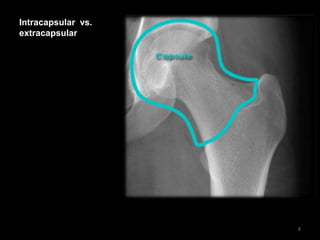

Intracapsular vs.

extracapsular

• The capsule

envelopes the